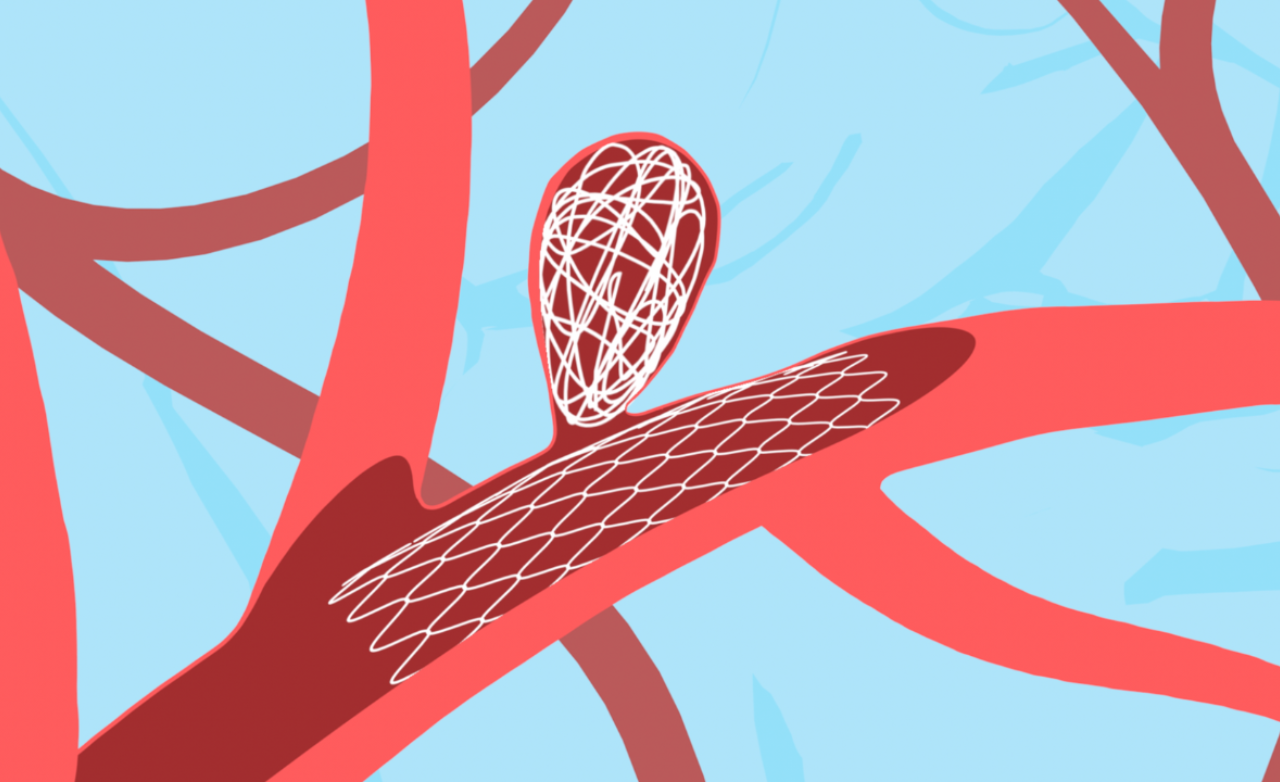

Minimally invasive technique using soft coils to block aneurysm flow, preventing rupture and ensuring long-term vascular stability.

Provides support for wide-neck aneurysms, ensuring secure coil placement and safer, more effective treatment.

Enhances treatment by redirecting blood flow away from the aneurysm, promoting gradual healing, improving vessel stability, and ensuring stronger, durable protection against future rupture.

Placed directly inside the aneurysm sac, these devices offer targeted treatment with minimal vessel manipulation for improved safety.